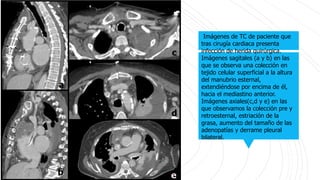

Imágenes de TC de paciente que

tras cirugía cardiaca presenta

infección de herida quirúrgica.

Imágenes sagitales (a y b) en las

que se observa una colección en

tejido celular superficial a la altura

del manubrio esternal,

extendiéndose por encima de él,

hacia el mediastino anterior.

Imágenes axiales(c,d y e) en las

que observamos la colección pre y

retroesternal, estriación de la

grasa, aumento del tamaño de las

adenopatías y derrame pleural

bilateral.